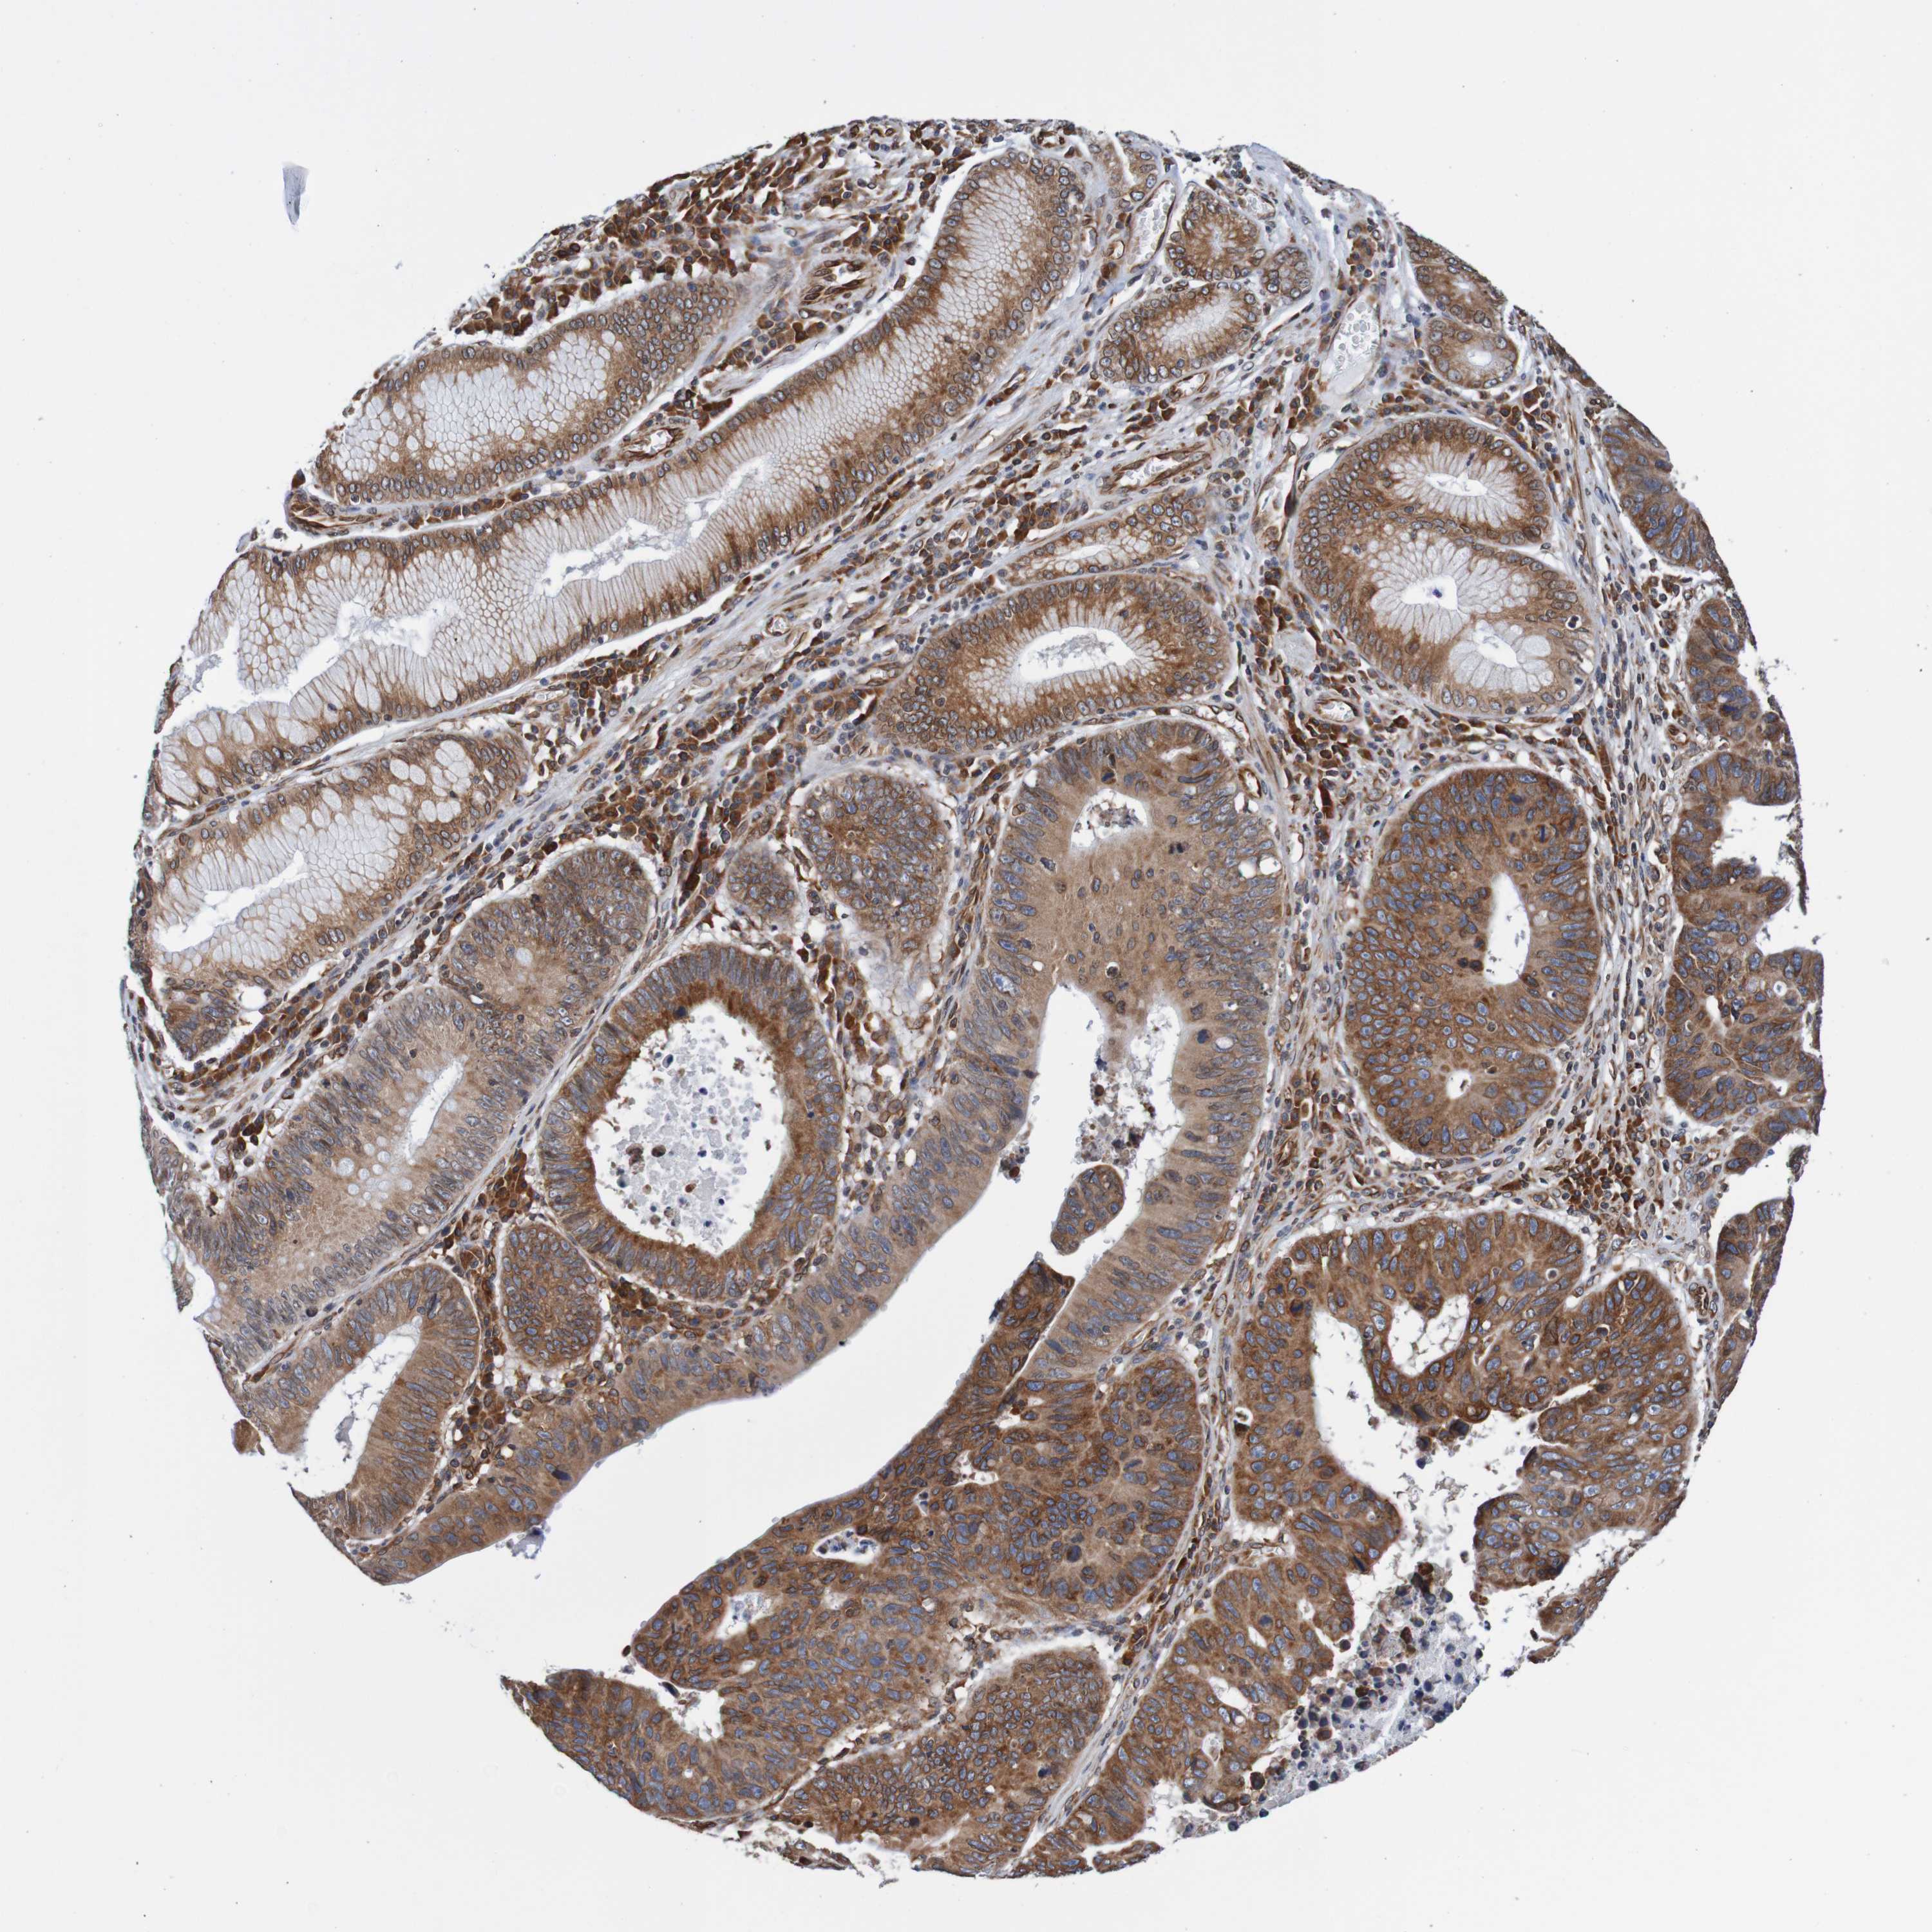

STOMACH CANCER - Protein expressioni

A mouse-over function shows sample information and annotation data. Click on an image to view it in a full screen mode. Samples can be filtered based on level of antibody staining by selecting one or several of the following categories: high, medium, low and not detected. The assay and annotation is described here.

Note that samples used for immunohistochemistry by the Human Protein Atlas do not correspond to samples in the TCGA dataset.

Antibody stainingi

Antibody staining in the annotated cell types in the current human tissue is reported as not detected, low, medium, or high, based on conventional immunohistochemistry profiling in selected tissues. This score is based on the combination of the staining intensity and fraction of stained cells.

Each image is clickable and will lead to virtual microscopy that enables deeper exploration of all samples and also displays staining intensity scores, fraction scores and subcellular localization as well as patient and tissue information for each sample.

Antibody HPA011785

Staining

High

Medium

Low

Not detected

Intensity

Strong

Moderate

Weak

Negative

Quantity

>75%

75%-25%

<25%

None

Location

Nuclear

Cytoplasmic/membranous

Cytoplasmic/membranous,nuclear

Adenocarcinoma, NOS

Adenocarcinoma, High grade